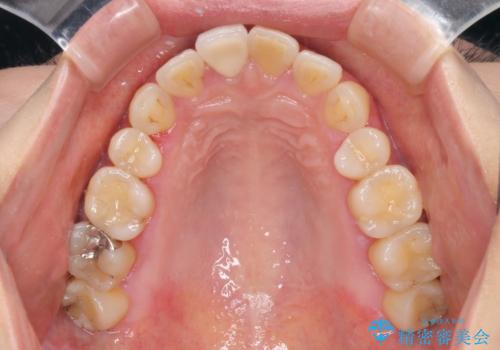

オールセラミッククラウンの治療を行いました。

また、右上の前歯は裏側までヒビが入っていることや、1層構造のラミネートよりも2層構造のオールセラミッククラウンの方が色の再現性も高いことから、右上前歯1本のクラウン治療をおすすめしました。

患者様には大変満足して頂きました。